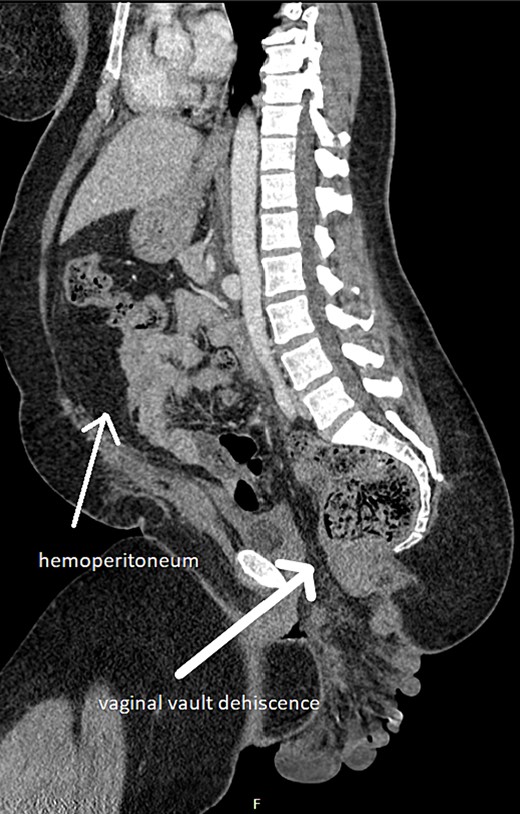

On examination, she was haemodynamically unstable with signs of acute abdomen and dusky-looking bowel protruding through her vaginal vault. Computed tomography (CT) showed small bowel evisceration through the vagina (Fig. 1). Multiple loops were seen outside the pelvic floor, with poor degree of perfusion and submucosal oedema. Lobulated hyperdensity tracking around small bowel loops suggested intra-abdominal haemorrhage.

Small bowel evisceration through vaginal vault dehiscence and haemoperitoneum on CT.